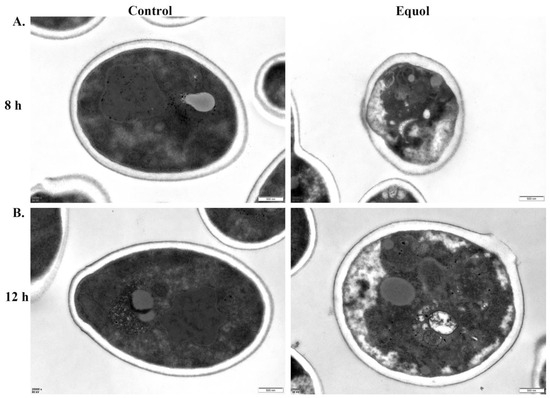

3.2. Equol Caused Ultrastructural Changes to Fungal Cells

The TEM analysis showed that the untreated cell wall, cell membrane, and cytoplasm were dense with complete structures and boundaries of the organelles. In addition, the fungal cells were round or oval with a uniform size. However, after exposure to Equol at 250 μg/mL for 8 and 12 h, the fungal cytoplasm was loose, the organelle structures were disorganized, the number of vacuoles was increased, the cell membrane was zigzagged and uneven, and the cell wall was destroyed, allowing for leakage of intracellular substances. These findings suggest that Equol caused morphological changes to the fungal cells and destroyed the surface structure (Figure 2), resulting in intracellular imbalance and inhibition fungal cell growth.

Figure 2. TEM results of C. albicans ATCC MYA-2876. C. albicans ATCC MYA-2876 treated with Equol (250 μg/mL) for 8 h (A) and 12 h (B). Scale bar: 500 nm.

The cell wall not only plays an important role in the maintenance of cell morphology and polarized growth, but also in adhesion with host cells and phagocytosis [45,46]. Previous investigations have demonstrated that antifungal drugs, such as echinocandins and β-glucan derivatives, target with the cell wall and enhance intracellular ROS levels, thereby achieving an inhibitory effect against fungal cells [47,48]. In this study, observations by TEM showed that treatment with Equol severely damaged the integrity of the fungal cell wall (Figure 2 and Figure 3). In addition to the cell wall, the cell membrane also plays an important role in maintaining and regulating the cellular structure and function [49,50,51]. The fluorescence staining results indicated that Equol also disrupted the integrity of the cell membrane (Figure 3). Therefore, the disruption of the cell wall and membrane by Equol would cause changes to fungal cell permeability and the intracellular environment. However, changes to the intracellular environment must be further confirmed.